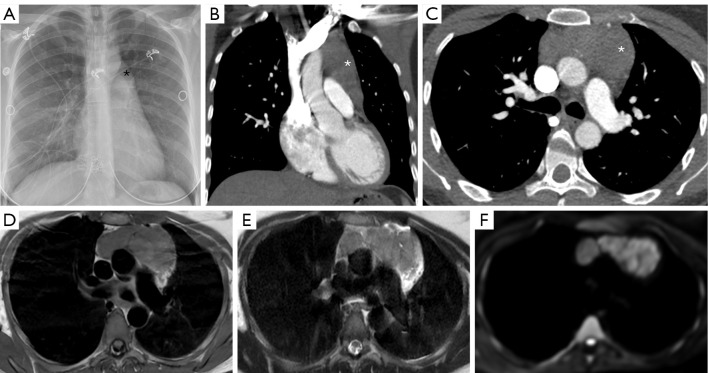

Abstract Image